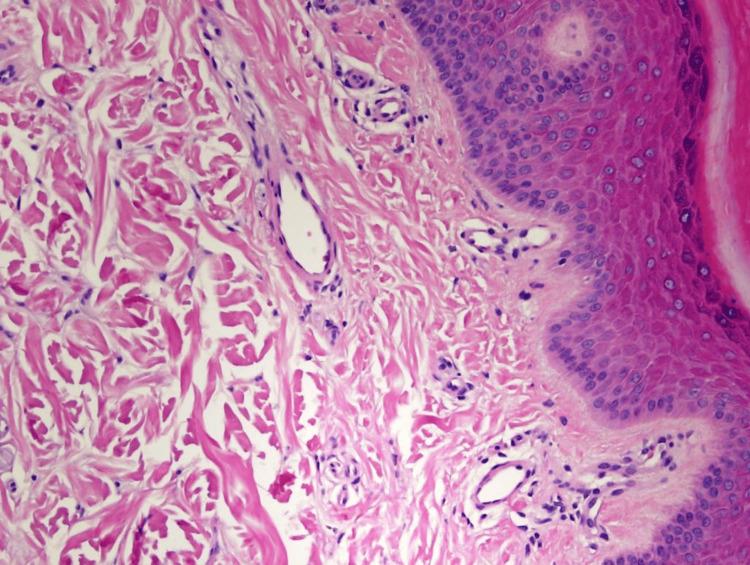

Sneddon syndrome, also known as livedo reticularis with cerebrovascular accidents, is a rare but chronic condition that affects blood vessels in the skin and brain. This syndrome is characterized by a net-like appearance on the skin, known as livedo reticularis, which occurs due to the constriction of blood vessels. In addition to skin manifestations, Sneddon syndrome is often associated with repeated neurological events, such as strokes or transient ischemic attacks. These neurological symptoms can vary in severity and can lead to various complications. Upon admission to the stroke unit, a 28-year-old female was found to have bilateral livedo reticularis affecting the soles and the dorsal sides of the hands. Patient evaluation is done through medical history, physical examination, routine laboratory tests, and other diagnostic procedures.

斯内登综合征,也称为伴有脑血管意外的网状青斑,是一种罕见的慢性疾病,会影响皮肤和大脑中的血管。这种综合征的特征是皮肤上出现网状外观,即网状青斑,这是由血管收缩引起的。除了皮肤表现外,斯内登综合征还常与反复的神经系统事件相关,如中风或短暂性脑缺血发作。这些神经症状的严重程度各不相同,并可能导致各种并发症。一名28岁女性入住卒中单元时,被发现双侧网状青斑累及足底和手背。通过病史、体格检查、常规实验室检查和其他诊断程序对患者进行评估。